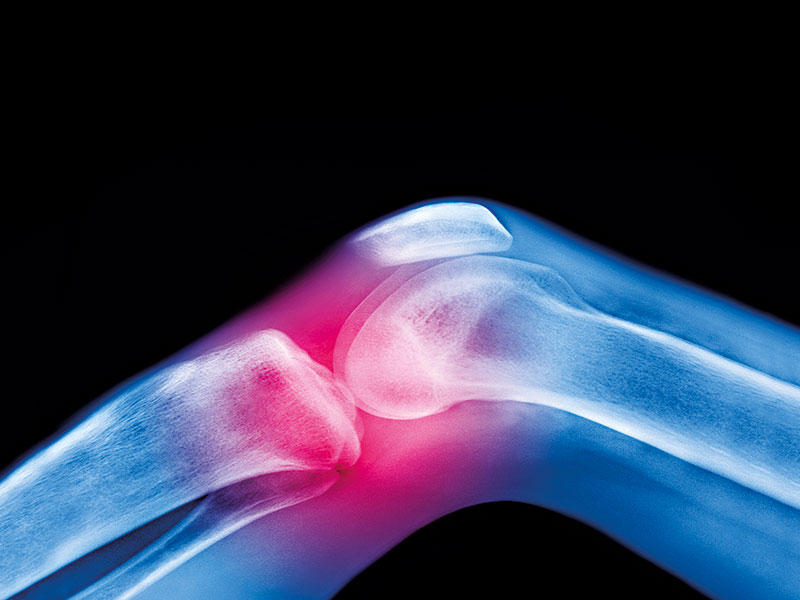

CO.DON develops, produces and markets autologous cell therapies – or, in layman’s terms, therapies that use only a patient’s own cells – to repair cartilage defects in the knee through a minimally invasive method. To date, the treatment has been used in over 200 clinics to treat more than 12,000 patients. Despite this fact, however, Jakobs believed there was a distinct lack of trust in the potential of the product when he first arrived, as well as a lack of belief in the team’s own capabilities.

At CO.DON, we’ve had to make a number of tough portfolio decisions in the past six years and this has led us to focus on just one specific treatment area: cartilage repair with autologous human cells. This change was a strategic decision to transform CO.DON from a typical biotechnology company into a biopharmaceutical enterprise. As a result, our product represents the highest level of personalised medicine – an area that even big pharmaceutical companies have failed to succeed in so far.